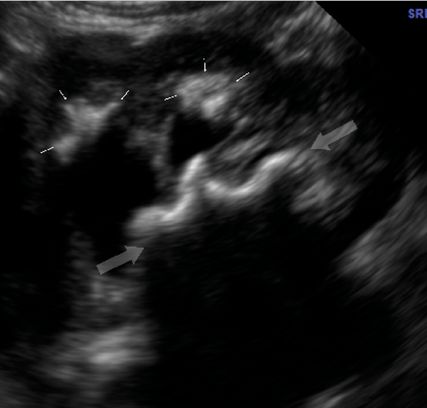

Abb. 2: 3-jähriges Mädchen, Ultraschall der linken Niere mit der – nach unserer Erfahrung vergleichsweise seltenen – Kombination aus Stein (Blockpfeile) mit Schallschatten und Nephrokalzinose (schlanke Pfeile), hier wegen der Hydronephrose gut zu unterscheiden. Klinisch und laborchemisch wurde am Lebensanfang eine infantile Hyperkalziämie mit Hyperkalziurie und erniedrigtem Parathormon diagnostiziert. Die Genetik ergab aber keine dahingehend bekannte Mutation

Zusätzliche Unklarheit stiftet eine begriffliche Problematik: Nephrolithiasis und Nephrokalzinose (Kalkablagerung in den Sammelrohren, sonografisch echoreiche Markpyramiden) klingen nicht nur ähnlich, sondern sehen im Ultraschall auch ähnlich aus (Abb. 2). Und: Die Begrifflichkeiten werden in der Pädiatrie zum Teil zusammengefasst; selbst in der einschlägigen pädiatrischen Literatur. Kinderärzt:innen sind im Zuge der Neonatologie regelmäßig mit der Nephrokalzinose konfrontiert. Diese bildet sich bei Frühgeborenen häufig spontan zurück (wie auch die weiter unten genannte renale Säuglings-Mikrolithiasis). Kinderärztliche „awareness“ für das Steinleiden ist daher von abwartender Haltung beeinflusst. Intraluminale Steine erfordern aber aktive Behandlung.

Ursächliche Erkrankungen können wir außerdem mittels Genetik präzisieren sofern das spezifische Problem des Individuums schon als Erkrankung bekannt ist. Wir finden aber auch bei massiv betroffenen Kindern immer wieder eine unauffällige Genetik (Abb. 2). Entsprechend ist das Panel bekannter Gene, die mit Harnsteinen und/oder Nephrokalzinose assoziiert sind, in ständigem Wandel begriffen und aktualisiert am besten online erhältlich (z.B. www.genetik.bioscientia.de/methoden/gen-panels/gen-panels-nieren/nephrokalzinose-und-nephrolithiasis-1/ ).